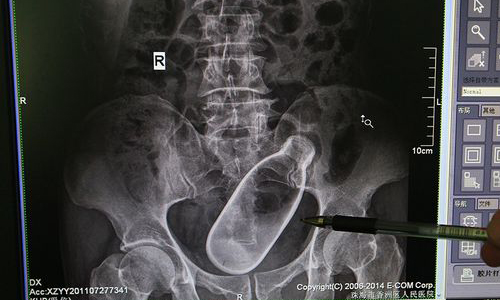

中國地大物博,離譜事件多不勝數,誇張程度一再超越自我極限,每每令人嘖嘖稱奇。廣東省珠海市一名60歲男性日前因腹痛就醫,X光圖令人驚訝地發現,他的下體塞了大瓶一只!

醫師表示,病患自稱下體有瓶的理由竟是受「排便困難」所困擾,因此拿異物來刺激肛門,以期通暢管路、終結苦難。沒料到收得反效果,便祕不但沒通,體內還進駐不速之客卡得死緊。由於瓶身已深入體內,老人無法憑一己之力取出,不得已只好尋求專業協助。

這張在X光圖照於2011年,近期才由院方曝光在網路上,火速跨國流傳。幸好當事人個資確實保密未外洩,不然可糗大了。另外,2014年初,福建省福州市亦發生過一起類似事件...